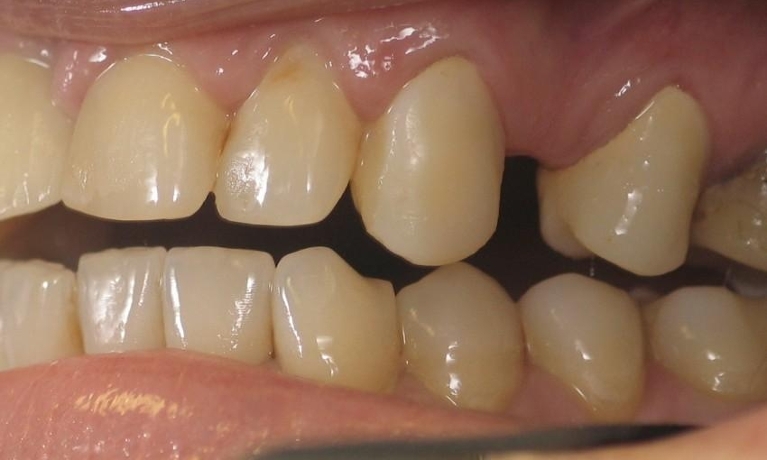

Smile Gallery

Are you considering dentistry at Michael J Nelson DDS? If so, we’d like to invite you to browse our Smile Gallery. Our dental team can improve your oral health and help you attain the attractive smile you’ve always wanted.